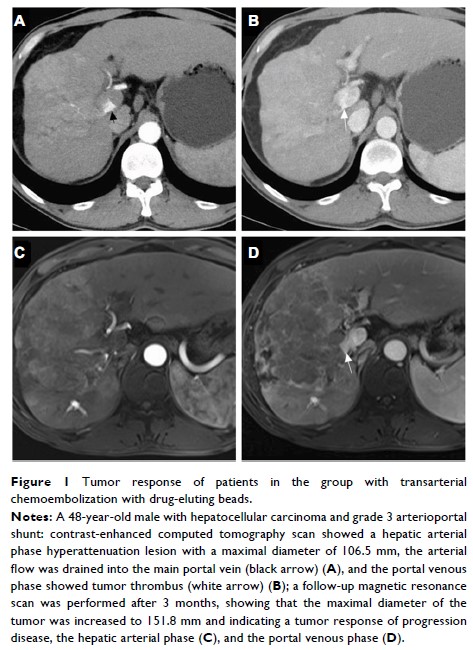

- 作者:Chao An, Xin Li, Ping Liang, Jie Yu, Zhigang Cheng, Zhiyu Han, Fangyi Liu, Linan Dong

- 期刊:Cancer Management and Research